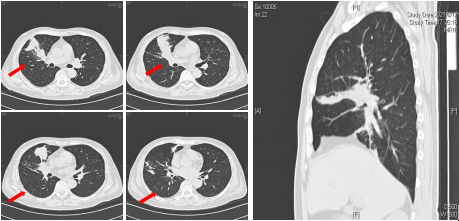

入院后查外周血白细胞减少 。 胸部CT可见右肺中叶、下叶多发斑片和片状渗出实变影(图1) 。

文章图片

图1入院胸部CT可见右肺中叶和右肺下叶内基底段可见多发斑片和片状肺内渗出实变影(箭头所示)